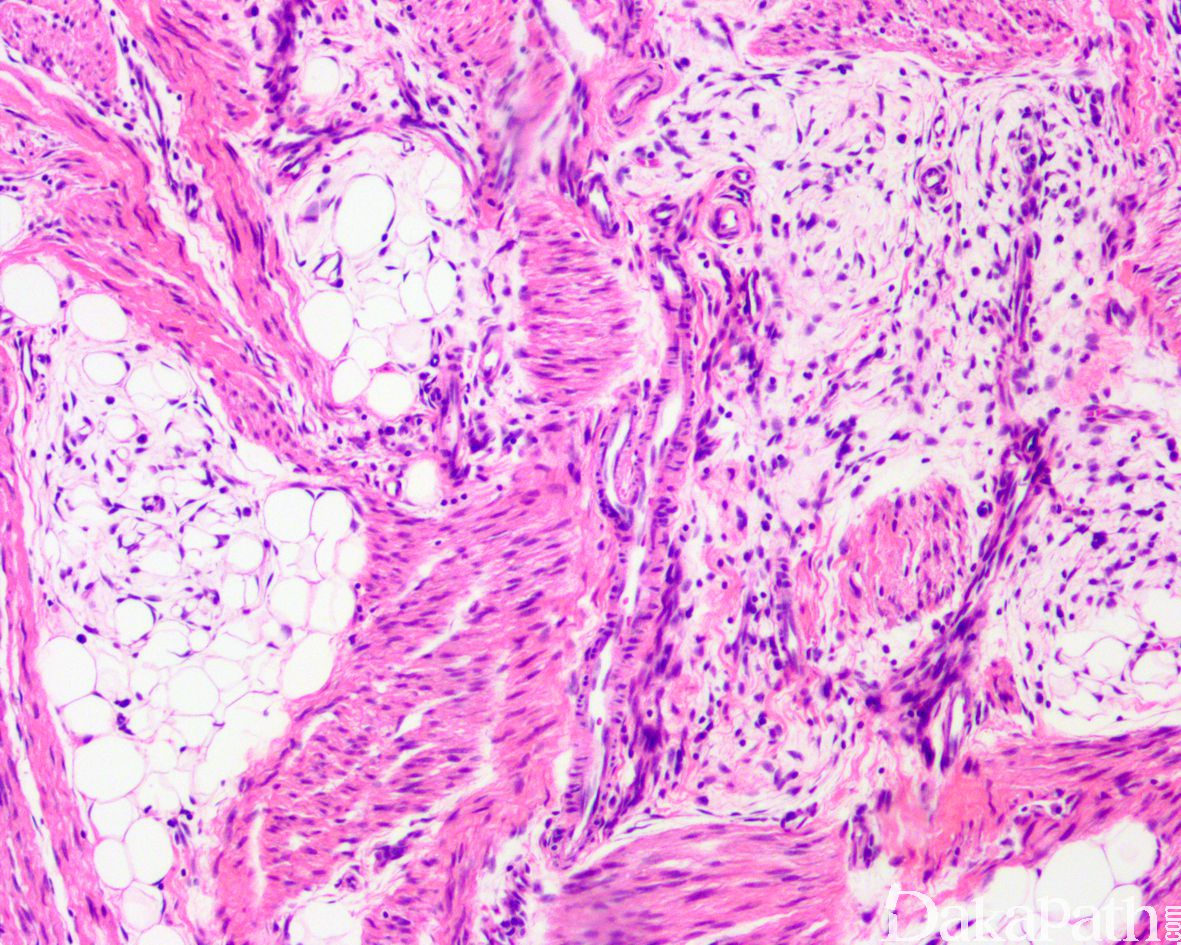

镜下位于真皮深层或皮下,边界不清;由致密梭形细胞、原始间叶细胞和成熟脂肪组织组成,不同病例三者比例不同:

致密的纤维组织由比较成熟的纤维母细胞、肌纤维母细胞和胶原纤维组成,呈纵横交错的束状排列,常呈指状伸入脂肪组织内,组织学类似于纤维瘤病;部分区域可见梭形细胞之间成片的胶原化或瘢痕化以及多核巨细胞沉积,类似于乳腺的假血管瘤样增生或巨细胞纤维母细胞瘤样改变;

原始间叶组织呈结节状分布,由幼稚的短梭形、卵圆形或星状细胞排列成呈疏松的漩涡状、巢状或宽带状包被于富于血管的黏液性基质之间;

瘤细胞形态均教温和,核异型性轻微,罕见核分裂象;